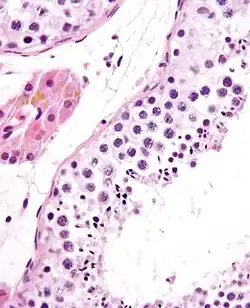

![]() A mature human Spermatozoon | |

Spermatidogenesis is the creation of spermatids from secondary spermatocytes. Secondary spermatocytes produced earlier rapidly enter meiosis II and divide to produce haploid spermatids. The brevity of this stage means that secondary spermatocytes are rarely seen in histological studies.

Spermiogenesis

During spermiogenesis, the spermatids begin to form a tail by growing microtubules on one of the centrioles, which turns into basal body. These microtubules form an axoneme. Later the centriole is modified in the process of centrosome reduction.[16] The anterior part of the tail (called midpiece) thickens because mitochondria are arranged around the axoneme to ensure energy supply. Spermatid DNA also undergoes packaging, becoming highly condensed. The DNA is packaged firstly with specific nuclear basic proteins, which are subsequently replaced with protamines during spermatid elongation. The resultant tightly packed chromatin is transcriptionally inactive. The Golgi apparatus surrounds the now condensed nucleus, becoming the acrosome.

Maturation then takes place under the influence of testosterone, which removes the remaining unnecessary cytoplasm and organelles. The excess cytoplasm, known as residual bodies, is phagocytosed by surrounding Sertoli cells in the testes. The resulting spermatozoa are now mature but lack motility. The mature spermatozoa are released from the protective Sertoli cells into the lumen of the seminiferous tubule in a process called spermiation.